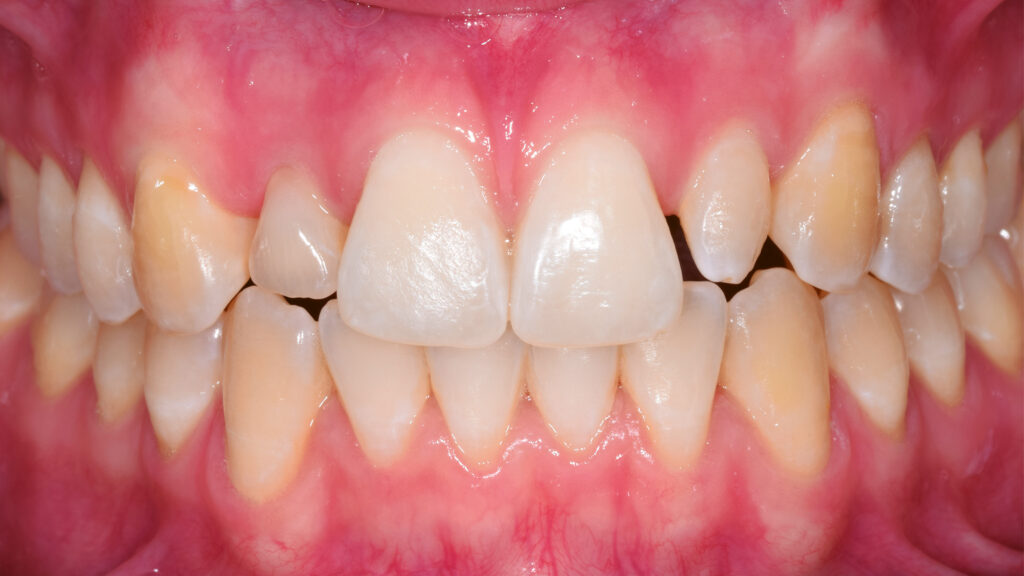

Ein Blick auf die Ausgangssituation (Abb. 1) verdeutlicht die Problematik bei diesem jungen Patienten. Der Milchzahn in regio 12 ist stark verfärbt. Zusätzlich beeinträchtigt der verkleinerte Zahn 22 (Mikrodontie) das ästhetische Bild. Auch der Gingivaverlauf erscheint unharmonisch. Abbildung 2 zeigt die Situation nach kieferorthopädischer Erstbehandlung. Während dieser Behandlungsphase konnte im Frontzahnbereich Platz für das Implantat (TiUltra, Nobel Biocare, Zürich, Schweiz) regio 12 und für das Keramikveneer an Zahn 22 geschaffen werden. Dies bildet die Grundlage für ein natürliches und harmonisches Erscheinungsbild.